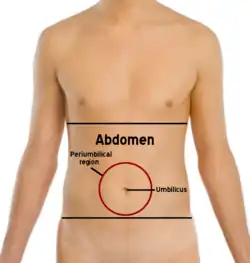

(Right) A male abdomen.

Surface landmarks

In the mid-line, a slight furrow extends from the xiphoid process above to the pubic symphysis below, representing the linea alba in the abdominal wall. At about its midpoint sits the umbilicus or navel. The rectus abdominis on each side of the linea alba stands out in muscular people. The outline of these muscles is interrupted by three or more transverse depressions indicating the tendinous intersections. There is usually one about the xiphoid process, one at the navel, and one in between. It is the combination of the linea alba and the tendinous intersections which form the abdominal "six-pack" sought after by many people.

Quadrants and regions

The abdomen can be divided into quadrants or regions to describe the location of an organ or structure. Classically, quadrants are described as the left upper, left lower, right upper, and right lower. Quadrants are also often used in describing the site of an abdominal pain.[15]

The abdomen can also be divided into nine regions.